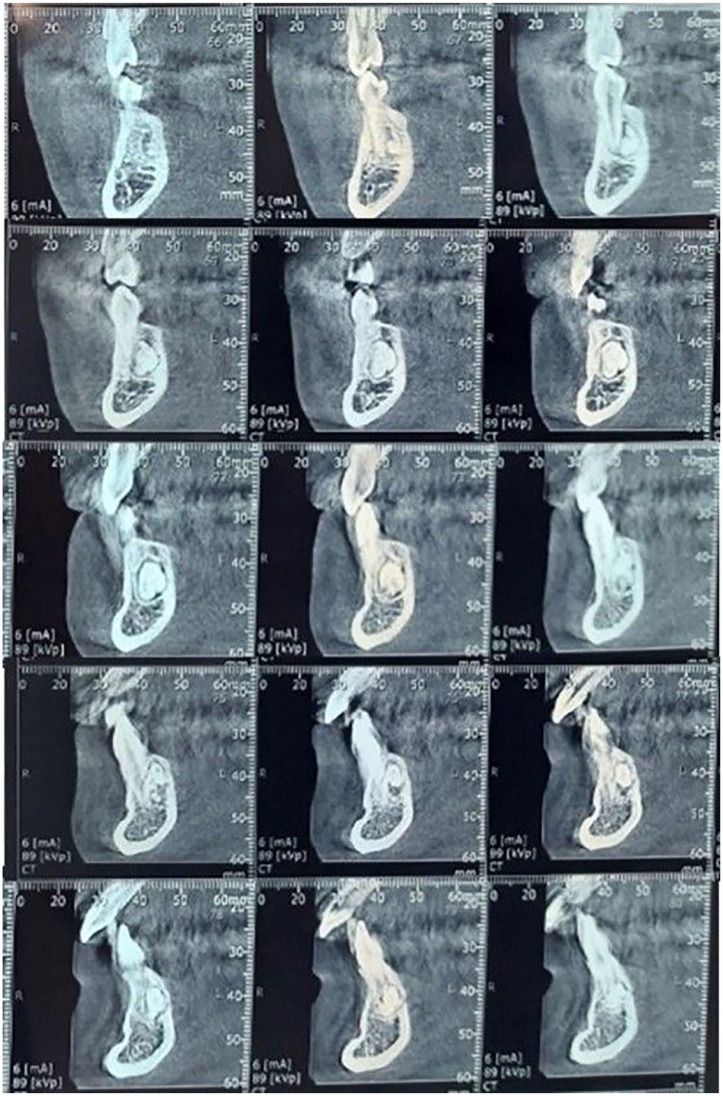

Calcifying odontogenic cyst, also known as Gorlin cyst is a rare benign cystic lesion primarily found in the jawbones, accounting less than 1% of odontogenic cysts. It can be associated with odontogenic tumors such as odontomas. We report a rare case of COC associated with complex odontoma in a young patient and discuss its clinical features, diagnosis, and treatment options. An 18-year-old female patient presented with a painless radiopaque lesion of the right mandibular bone at Oral Medicine and Oral Surgery department. Radiographs revealed irregular tooth-like structures in the canine-premolar area. The lesion was surgically removed, and histopathology confirmed COC with a complex odontoma. As of the World Health Organization's 2022 definition, COC is a developmental odontogenic cyst characterized by calcified ghost cells. It typically affects individuals during their second and third decades of life, with no gender preference, almost equally in the maxilla and the mandible. The main treatment is total enucleation, with a generally favorable prognosis. Histopathology is essential for diagnosis due to its mimicry of other jaw conditions. Long-term follow-up is needed to prevent recurrences.

Abstract Image